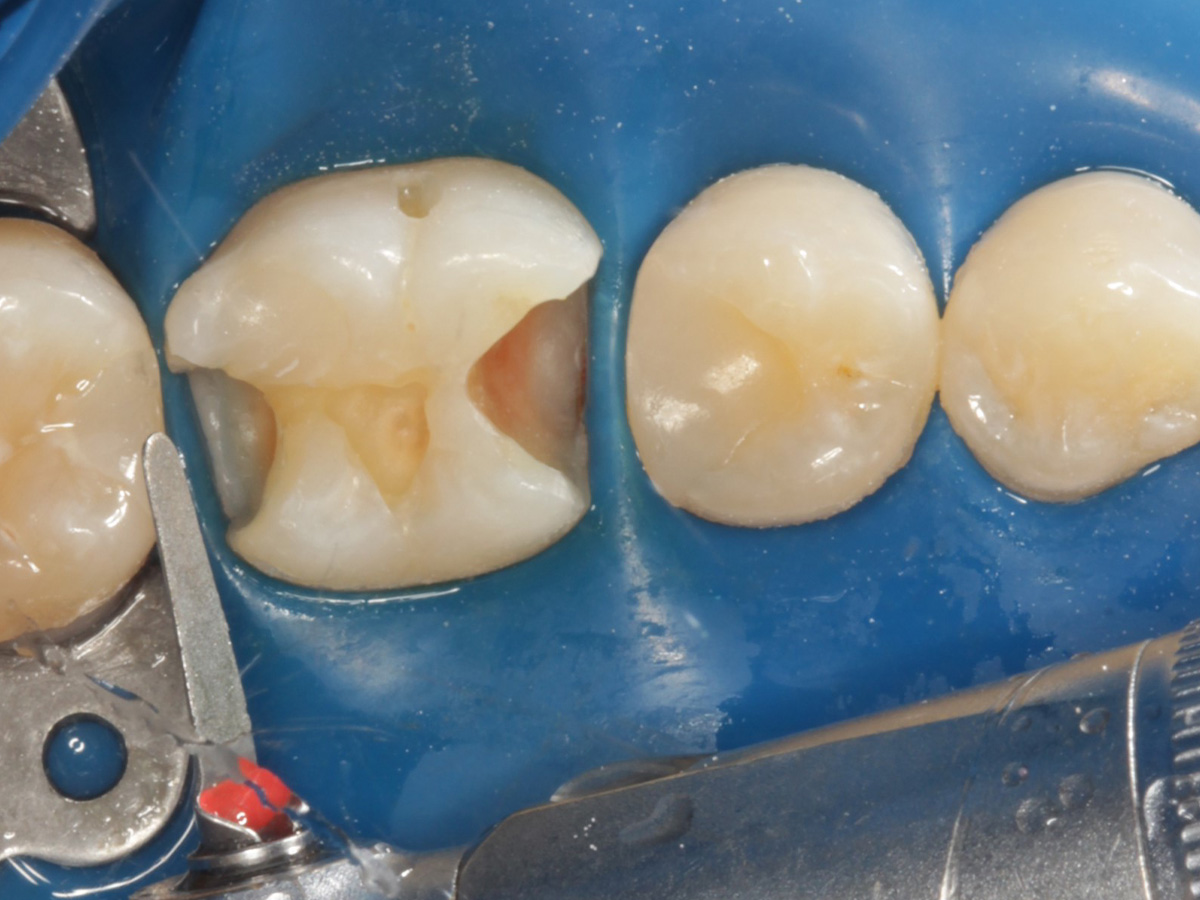

Abbildung 4

Defektdarstellung; „Schutzmatrizen“ ideal als „Leitplanken“ bei der Zahnpräparation tief approximal bis in gesunde Zahnsubstanz